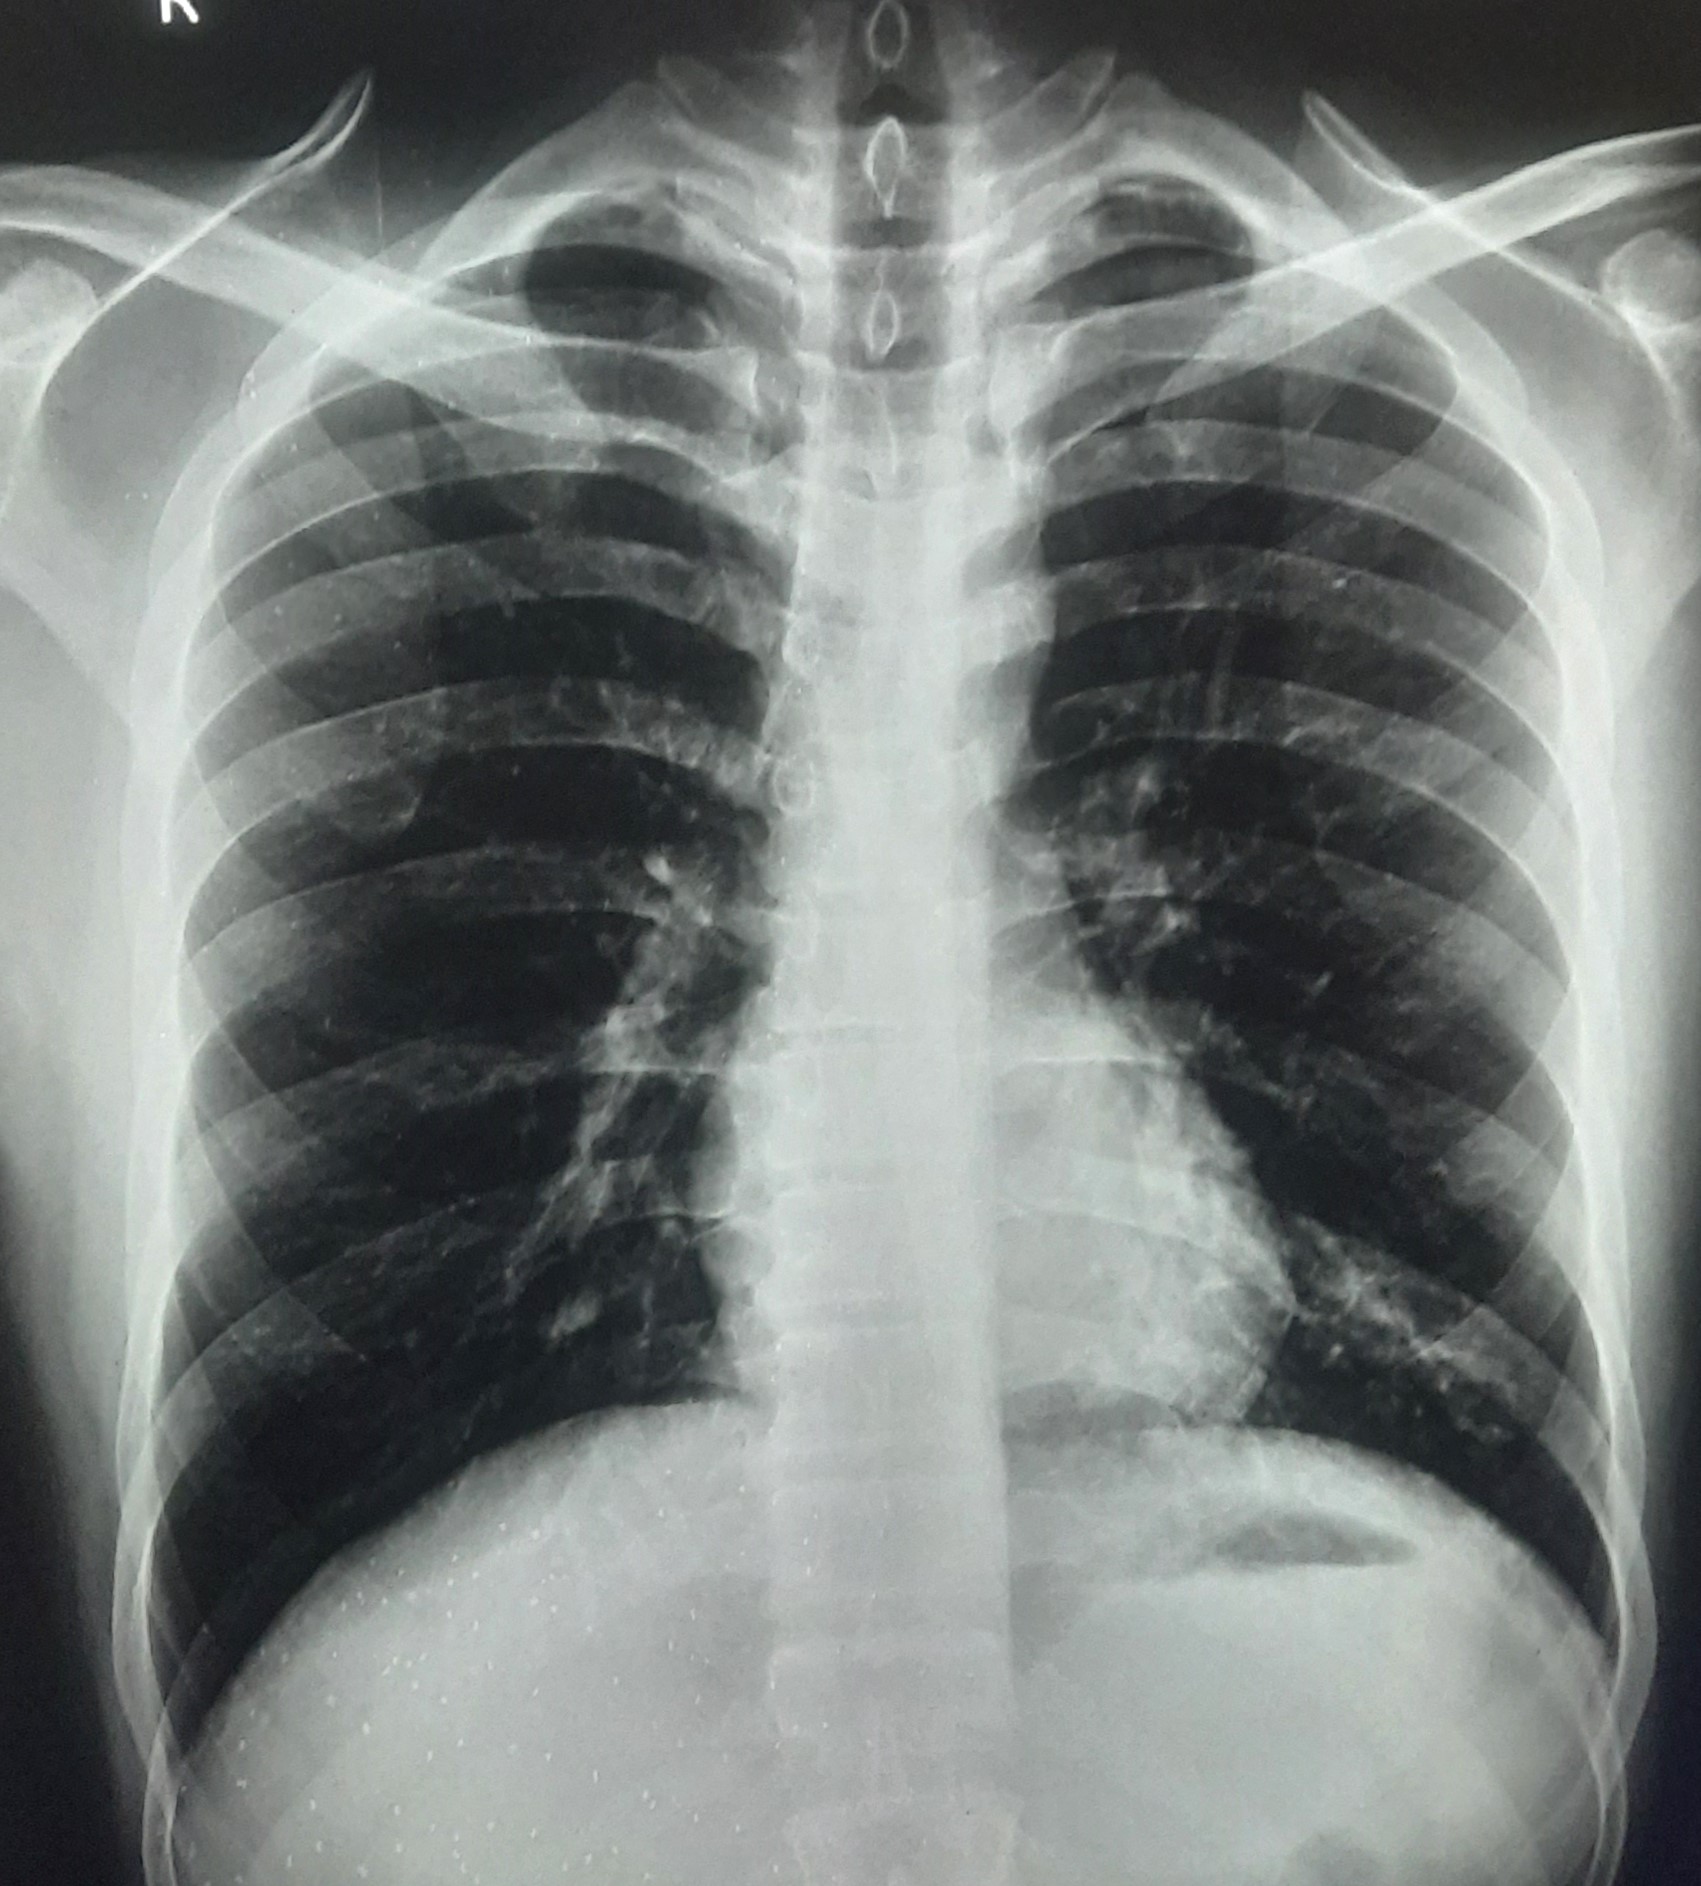

| 295 | IGGMC, Nagpur, Nagpur | P2 | 29-4177 | Afra Firdos | Consent taken on Paper | 14 Yrs. |

Provisional Diag : Pleural Effusion ?

Final Diag : Pleural Effusion |

Result awaited (Suspected TB/Non-TB) | Right Sided Pleural Effusion | Abnormality visible on x-ray |